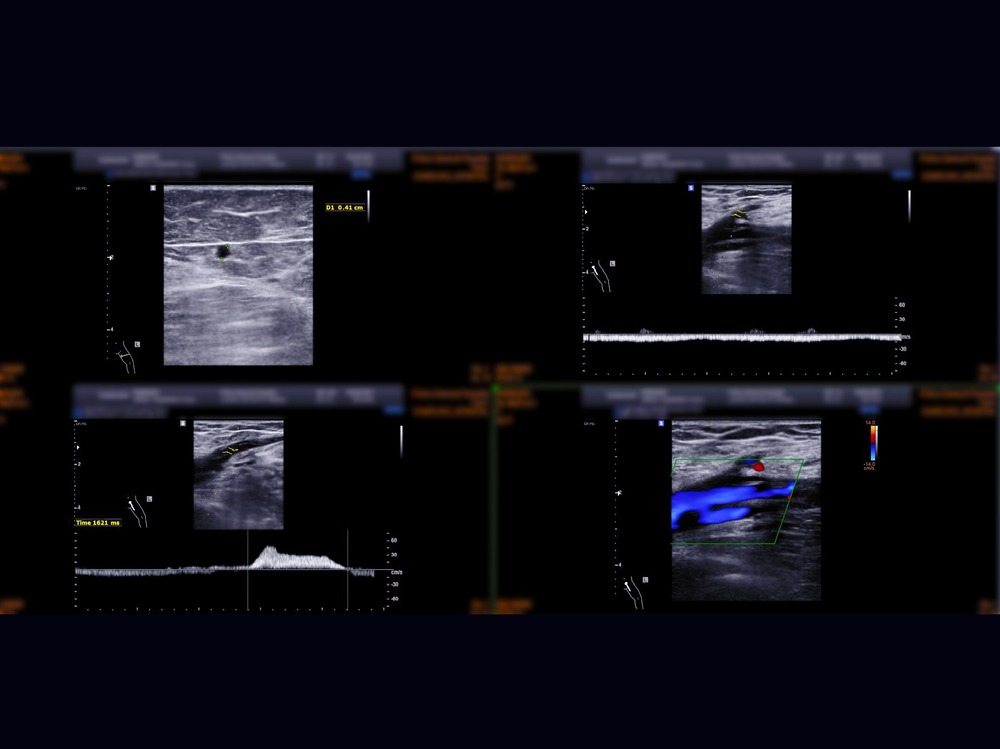

A Deep Vein Thrombosis scan is a non-invasive medical diagnostic imaging to check the presence of thrombus (blood clots) and blood flow in the large veins in the arms or legs. This scan also looks at superficial veins in the arms or legs if there are any blockage due to blood clots. However, the occurrence of blood clots is more common in the legs. This scan includes the assessment of femoral veins, sapheno-femoral junction, popliteal veins, sapheno-popliteal junction, and calf veins in your legs. It can help your healthcare professional to determine an immediate treatment in various conditions in your peripheral veins.

A Deep Vein Doppler ultrasound is a non-invasive medical diagnostic imaging to check the presence of thrombus (blood clots) and blood flow in the large veins in the arms or legs. This scan also looks at superficial veins in the arms or legs if there are any blockage due to blood clots. However, the occurrence of blood clots is more common in the legs. This scan includes the assessment of femoral veins, sapheno-femoral junction, popliteal veins, sapheno-popliteal junction, and calf veins in your legs. It can help your healthcare professional to determine an immediate treatment in various conditions in your peripheral veins.